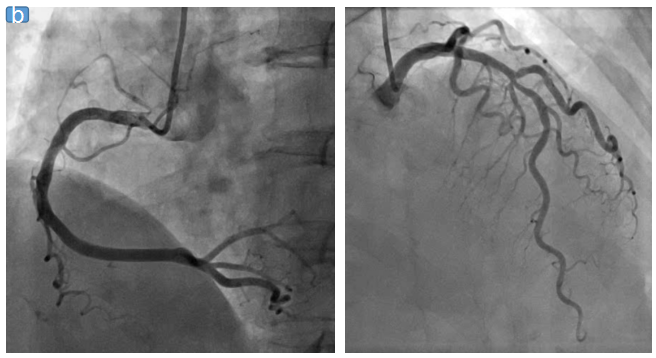

注:图a为冠状CTA图像;图b为冠状DSA图像